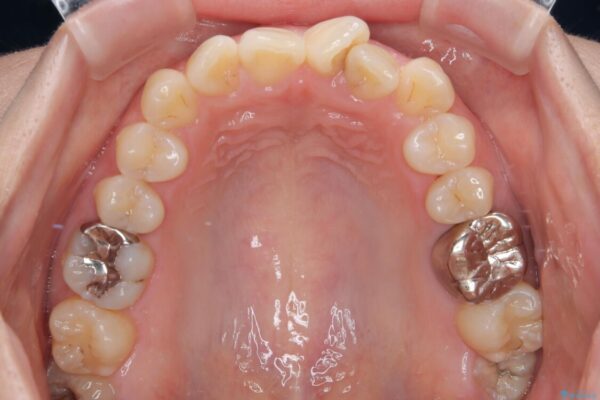

診察の結果、上下の前歯部に**叢生(そうせい/歯のガタガタ・重なり)**が認められました。

特に上の前歯にはねじれや重なりがあり、審美的にも清掃性にも影響している状態でした。

治療前

• 前歯のねじれ・ガタガタを10か月で改善!20代女性の矯正治療|クリアブラケットでむし歯になりにくい歯並びへ改善 治療前画像